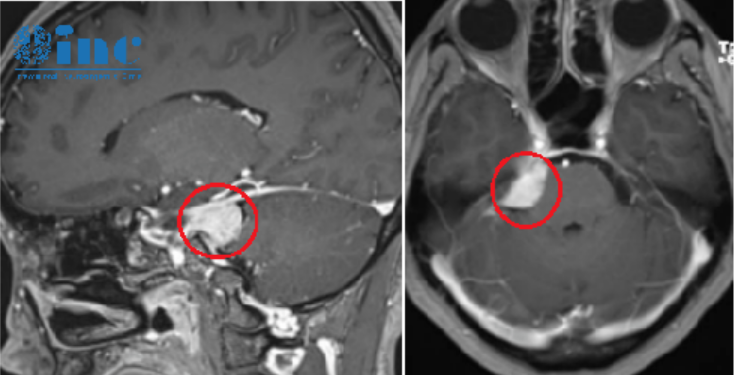

如果出現(xiàn)聽力損失、耳鳴或不平衡的癥狀,您可能會被咨詢到耳鼻喉科專家(ent)進行評估。通常,有了這些癥狀,你會被要求進行聽力測試。如果你頭暈,可能會進行額外的平衡測試。如果這些測試中的任何一項出現(xiàn)任何異常,表明功能不平等(不對稱聽力損失),您可能需要進行內(nèi)耳和頭部的MRI成像,以檢查是否有聽神經(jīng)瘤。MRI可以幫助準確診斷聽神經(jīng)瘤,因為這些腫瘤的特征與其他腦腫瘤相比顯得特別獨特。